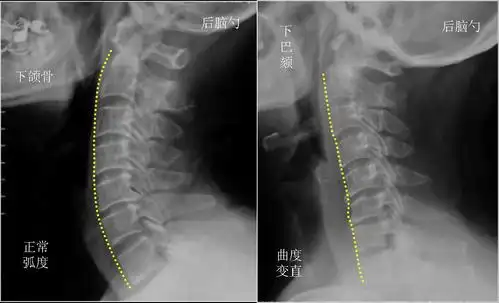

正在让我们的颈椎"生理曲度"

为什么颈椎生理曲度会变直会有什么严重后果吗

颈椎及椎间盘前缘高度变小等一系列改变, 最终出现颈椎曲度改变 (变直

注意一下你的颈椎弧度是否正确

颈椎生理曲度变直有什么危害性能够康复嘛